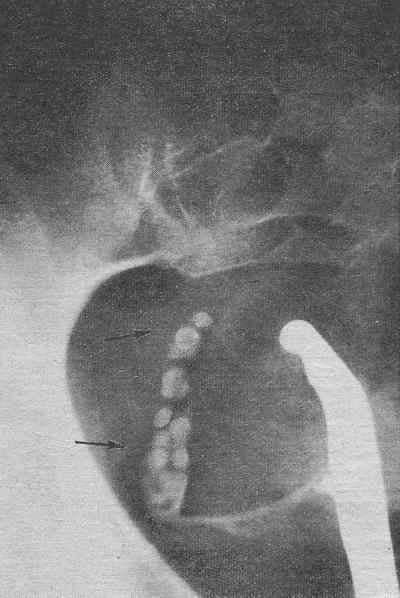

При хромоцистоскопія иидигокармин виділився з правого гирла на 5;ій хвилині інтенсивно забарвленої живий струменем, з лівого гирла забарвленої сечі протягом 20 хв спостереження не було помічено. Катетер, введений в лівий сечовід, зустрів перешкоду на висоті 4 см і вище не проходив. При вагінальному дослідженні у лівому бічному зводі промацувався щільний болючий інфільтрат розміром 2X3 див. На оглядовій рентгенограмі сечових шляхів у тазовому відділі лівого сечоводу визначалася група каменів (сім) розміром від 1,2X1,8 см до 0,3X0,4 див. На екскреторній урограмі через 7 і 15 хв після введення контрастної речовини фізіологічні порожнини правої нирки здійснилися нормально. Функція лівої нирки була зниженою. Визначалося значне розширення її Порожнинних відділів. На ретроградної пиелограмме контрастне речовина доходило до каменя і вище не піднімалося.

![]() Рис. 5. Хвора В-ва. Камені нижнього відділу лівого сечоводу. |

У зв'язку з відмовою від уретеролитотомии призначена комплексна консервативна терапія: пеніцилін по 150000 ОД 4 рази на день, олиметин по 1 капсулі 4 рази на день, короткохвильова діатермія на ліву клубову область і лікувальна фізкультура. Двічі була проведена новокаїн-гидрокортизоновая блокада лівої сечовідного гирла за нашою методикою. Через три дні після останньої блокади відійшло 7 каменів, розміри яких відповідали величині конкрементів на рентгенограмах (рис. 5). Через півроку хвора була обстежена амбулаторно. Функція нирок за индигокармину і на екскреторній урограмі була задовільною. Зліва відзначалася помірна піелоектазія. В осаді сечі лейкоцитів було 3-5 в полі зору. Рекомендовано санаторно-курортне лікування в Трускавці та продовження лікування пієлонефриту в амбулаторних умовах.